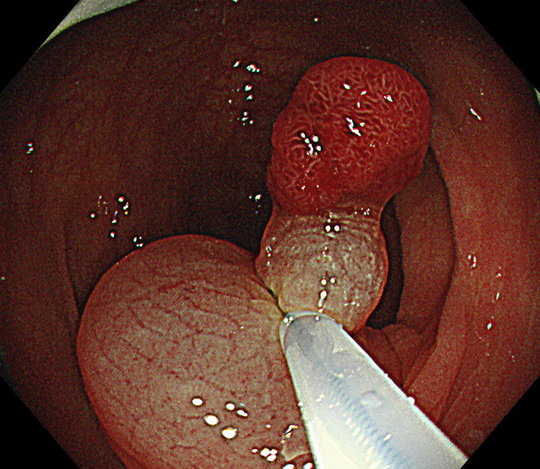

④診断結果に基づき内視鏡治療

AI診断も利用しますが、経験豊富な内視鏡専門医がしっかり診断し安全で確実な治療を行います